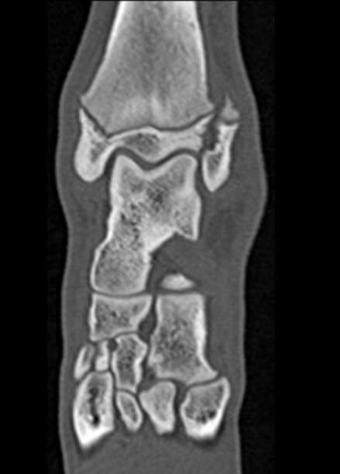

Gewrichten en gewrichtskapsel.

Carpus, ellebogen, schouder, Tarsus, knie, heupen.